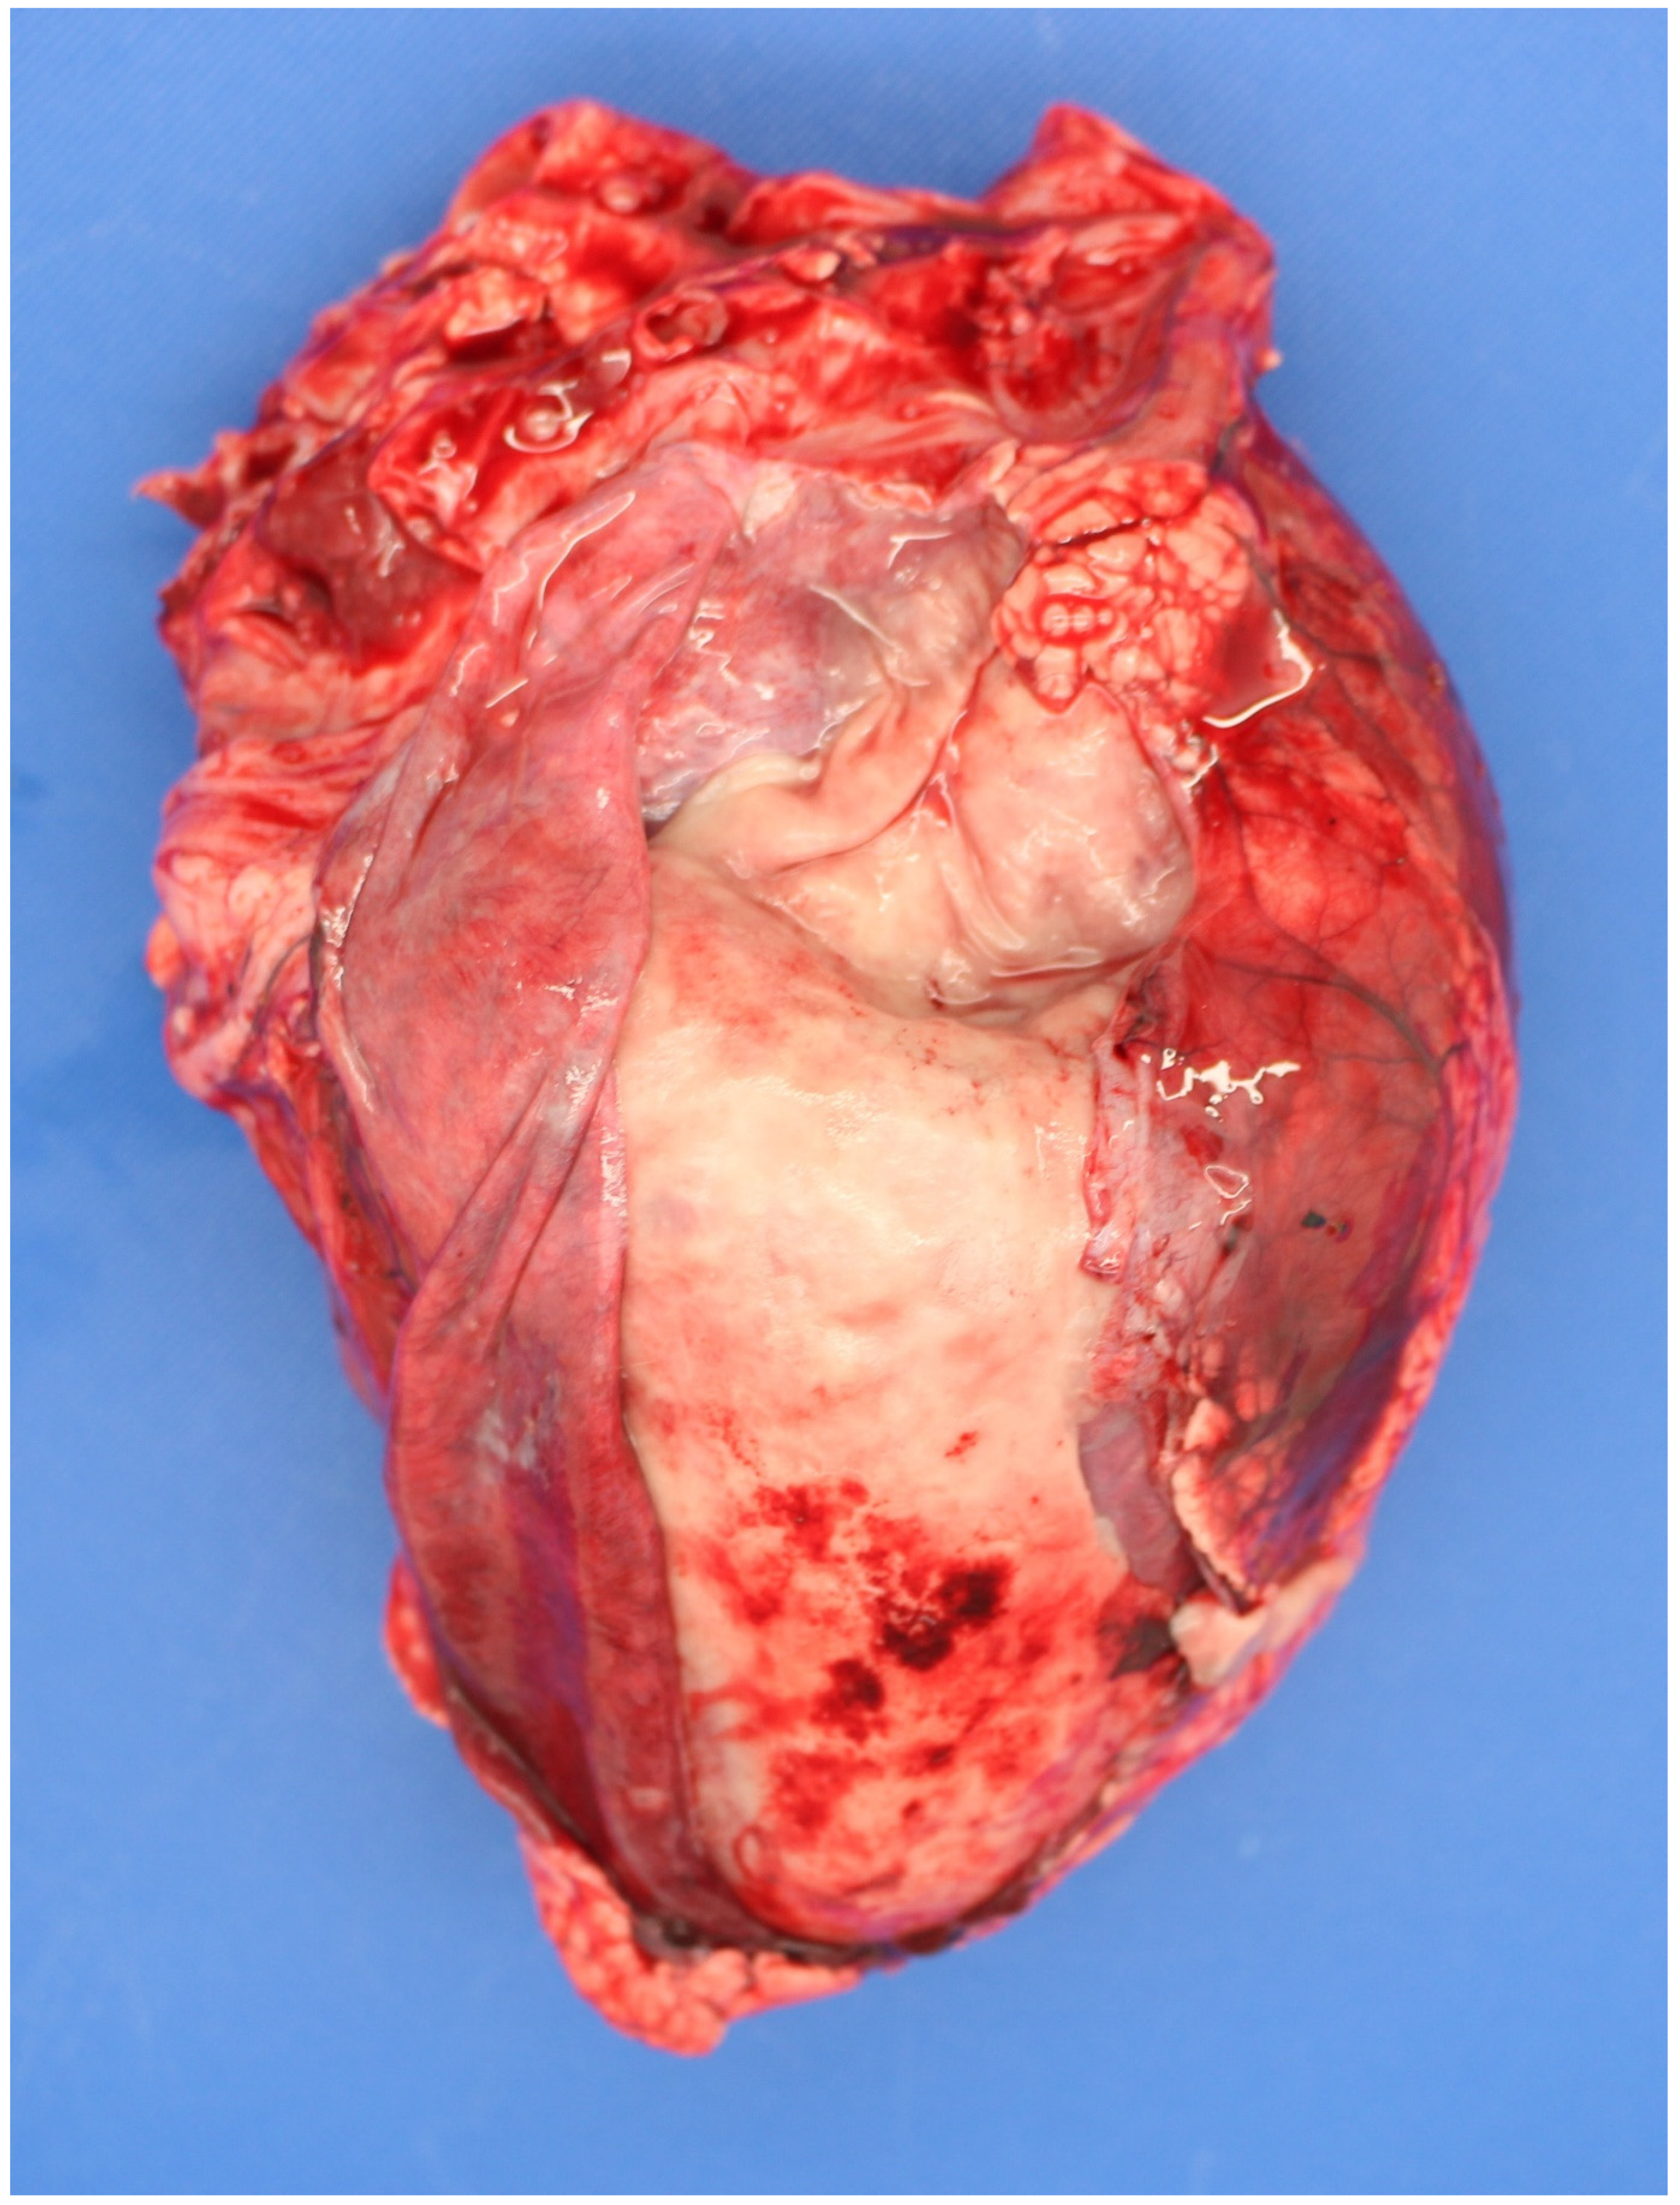

3.4. Examination of the Foetus

3.4.1. Sampling the Carcass

Microbiology Samples

3.5. Examination of the Placenta